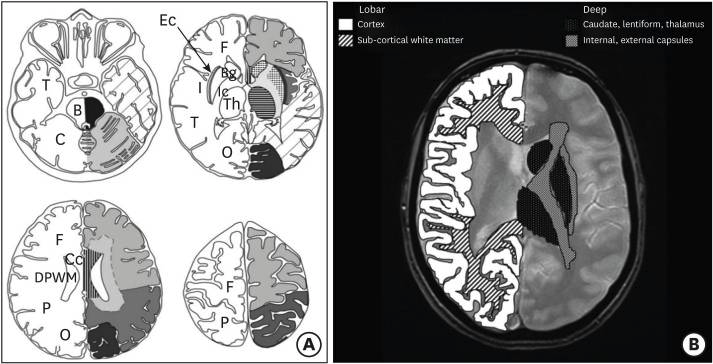

CMB를 평가할 때는 MARS(Microbleed Anatomical Rating Scal) 및 BOMBS(Brain Observer MicroBleed Scale)가 있다. 두 방법 모두 CMB는 위치에 따라 점수가 매겨진다. 두 방법의 차이는 MARS는 대뇌 영역이 각 엽(lobe)으로 구분되는 반면, BOMBS는 피질(cortex)과 피질하 영역(subcortical regions)으로 구분된다는 점에서 다르다.

최근 연구에서 CAA에 아밀로이드가 축적되면 혈관 공간이 확장되고 미세 출혈이 발생할 수 있는 것으로 추측된다고 한다. 알츠하이머 병에서 CMB는 주로 피질-피질하 경계에서 발생하며 알츠하이머병과 관련된 CAA에 의해 발생된다. 87% 이상의 CMB는 deep gray matter(심회백질)이나 brainstem(뇌간)이 아닌 lobar regions(대뇌엽 영역)과 주로 뇌의 posterior cortex(후방 피질)에 위치하며 CAA에 의해 발생할 가능성이 높다. 반면, 고혈압성 미세출혈은 주로 심회백질이나 뇌간에서 발생한다.